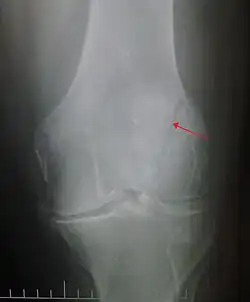

-

Osteochondral fracture of patella -

Some people have a normal bipartite patella or two-part patella which can appear as a fracture. The fragment is usually seen in the top outer corner of the patella and can be distinguished from a fracture by being present in both knees.[6]

The patella can break in various ways depending on the way it is injured, and into two or more pieces.[1] Types include transverse, the most common, with one fracture line;[5] marginal; osteochondral; and the rare vertical type, or stellate, where a direct compression force gives rise to a comminuted pattern.[5][7] Patella fractures can be further classified as displaced, where the broken ends of bone do not line up correctly and separate by more than 2mm, or undisplaced and stable where pieces of bone remain in contact with each other.[1][7] If fragments of patella bone stick out from the skin it is known as an open patella fracture, and closed if the overlying skin is intact.[1]